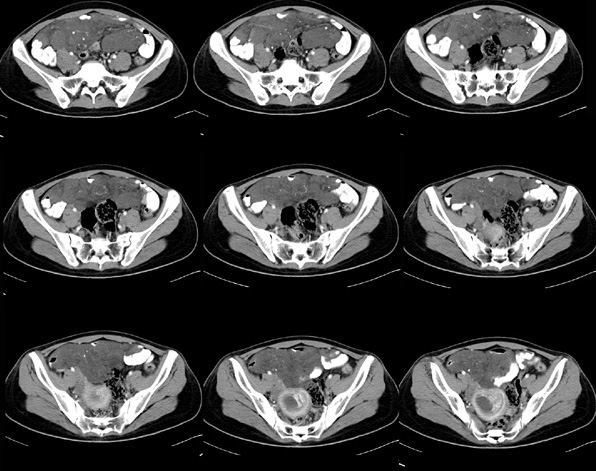

女性,28岁,停经3月,腹部膨隆1月,产前检查发现腹部占位

{肿块中心ct值27hu,增强后,动脉期、门脉期均无明显强化)

1 肠系膜肿块诸期无明显强化,肠系膜血管包绕其中但其周围仍见脂肪称“脂肪环征”;2 肠系膜血管远端较近端细,于重组像上见血管周围有强化结节为炎性结节,3肿块内见部分脂肪密度及少许点状钙化。4 腹膜后无肿大ln。

患者手术病理:腹腔囊性淋巴管瘤,象这样充满整个腹腔的的确很少见